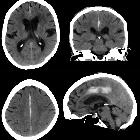

Subdural

hemorrhage • Parafalcine subdural hemorrhage - Ganzer Fall bei Radiopaedia

Parafalzines

Subduralhämatom mit zusätzlicher Subarachnoidalblutung beidseits nach Sturz.